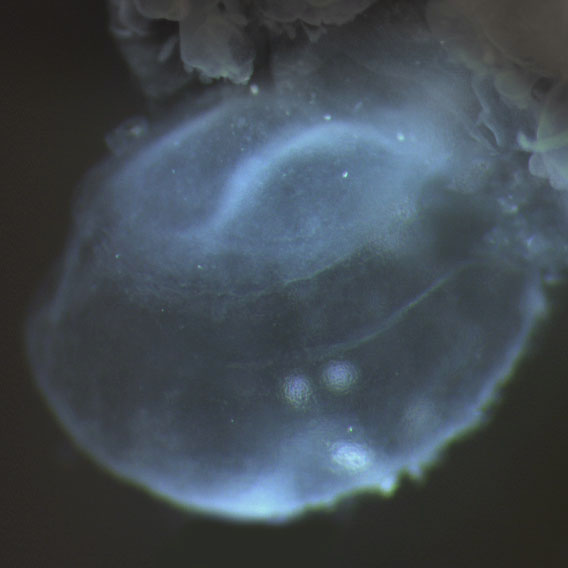

Carnegie Stage 8

Carnegie Stage 8 Definition

Age is approximately 23 postovulatory days

Length is approximately 1 - 1.5mm

External Features Include: the appearance of the primitive pit and the notochordal canal. Somites are not yet visible.